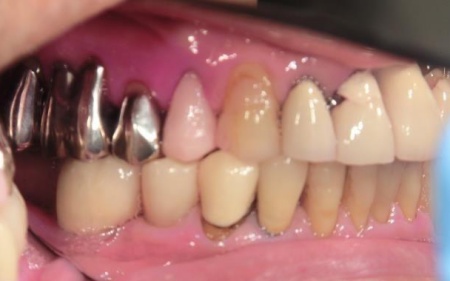

この治療のリスクについて

・外科手術のため、術後に痛みや腫れ、違和感を伴います

・メンテナンスを怠ったり、喫煙したりすると、お口の中に大きな悪影響を及ぼし、インプラント周囲炎などにかかる可能性があります

・糖尿病、肝硬変、心臓病などの持病をお持ちの場合、インプラント治療ができない可能性があります

・自費診療(保険適用外治療)です

・持病をお持ちの方や、服用中のお薬の種類によっては、外科処置ができない場合があります

・外科処置後のメンテナンスを怠ると、良好な結果が得られない可能性があります

- 年齢・性別 70代男性

- 診療種別 自由診療

- 治療期間の目安 約5ヶ月

- 治療費総額の目安 約350,000円